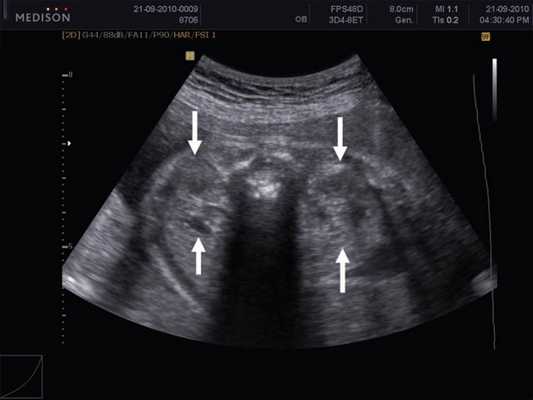

Под диафрагмой справа визуализировалось гиперэхогенное опухолевидное образование несколько неоднородной солидной структуры, с четкими ровными контурами, размером 50x38x35 мм. К нижнему полюсу данного образования прилежала правая почка, имеющая нормальные размеры, форму и структуру. Нижняя полая вена была смещена кпереди и влево. Обращала на себя внимание выраженная гепатомегалия, причем структура печени не была однородной. Она содержала множественные гиперэхогенные включения размерами до 17 мм, окруженные тонким гипоэхогенным периферическим ободком. Цветовое допплеровское картирование(ЦДК) демонстрировало интенсивную периферическую васкуляризацию опухоли (рис. 1-3).

Рис. 3. Метастазы в печени плода. Поперечное сечение брюшной полости плода. Гепатомегалия. В структуре печени плода определяются округлые включения несколько повышенной эхогенности (стрелки), с гипоэхогенным ободком - метастазы.